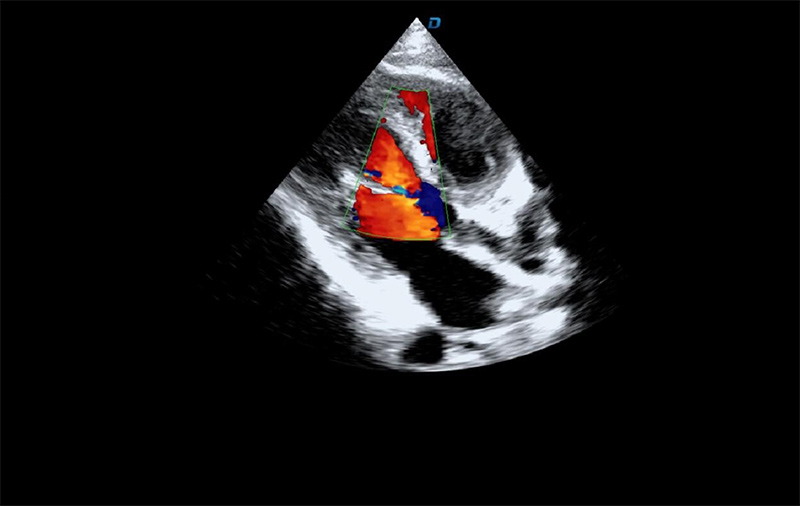

心臟彩超機檢查

有些心臟病會引起心臟電活動的改變,但是有些心臟的疾病卻不影響心電,而只影響心臟本身的結(jié)構(gòu)。比如心臟擴大,心臟收縮無力,心臟的瓣膜關(guān)閉不嚴(yán)密,這些疾病的診斷及發(fā)現(xiàn)更多的依賴于心臟彩超,這些病變一般不隨癥狀的緩解而緩解。心臟超聲心動圖,不需要開胸,就可以看到心臟的大小、內(nèi)部結(jié)構(gòu)、瓣膜運動情況等。除了探頭壓迫可能會有疼痛或不適感外,對患者沒有任何創(chuàng)傷。

臨床上,心臟超聲心動圖主要用于對各種先心病、心臟瓣膜病的診斷;各種心肌病、心包疾病的診斷和心臟功能的評估。部分嚴(yán)重肺氣腫、胸廓畸形等患者,因為超聲圖像質(zhì)量欠佳而診斷效果受到一定限制。